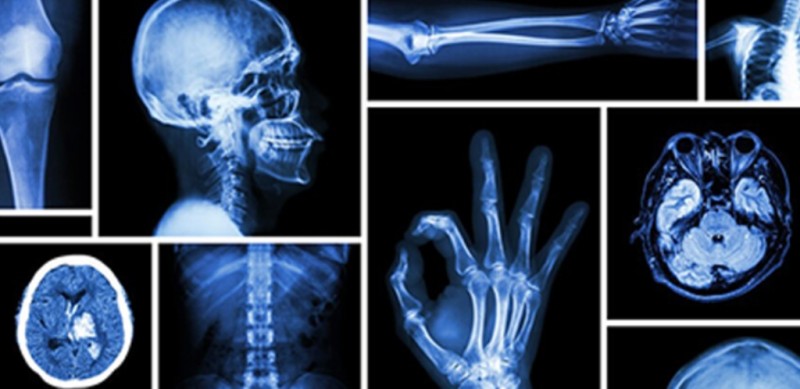

महिला स्वास्थ्य